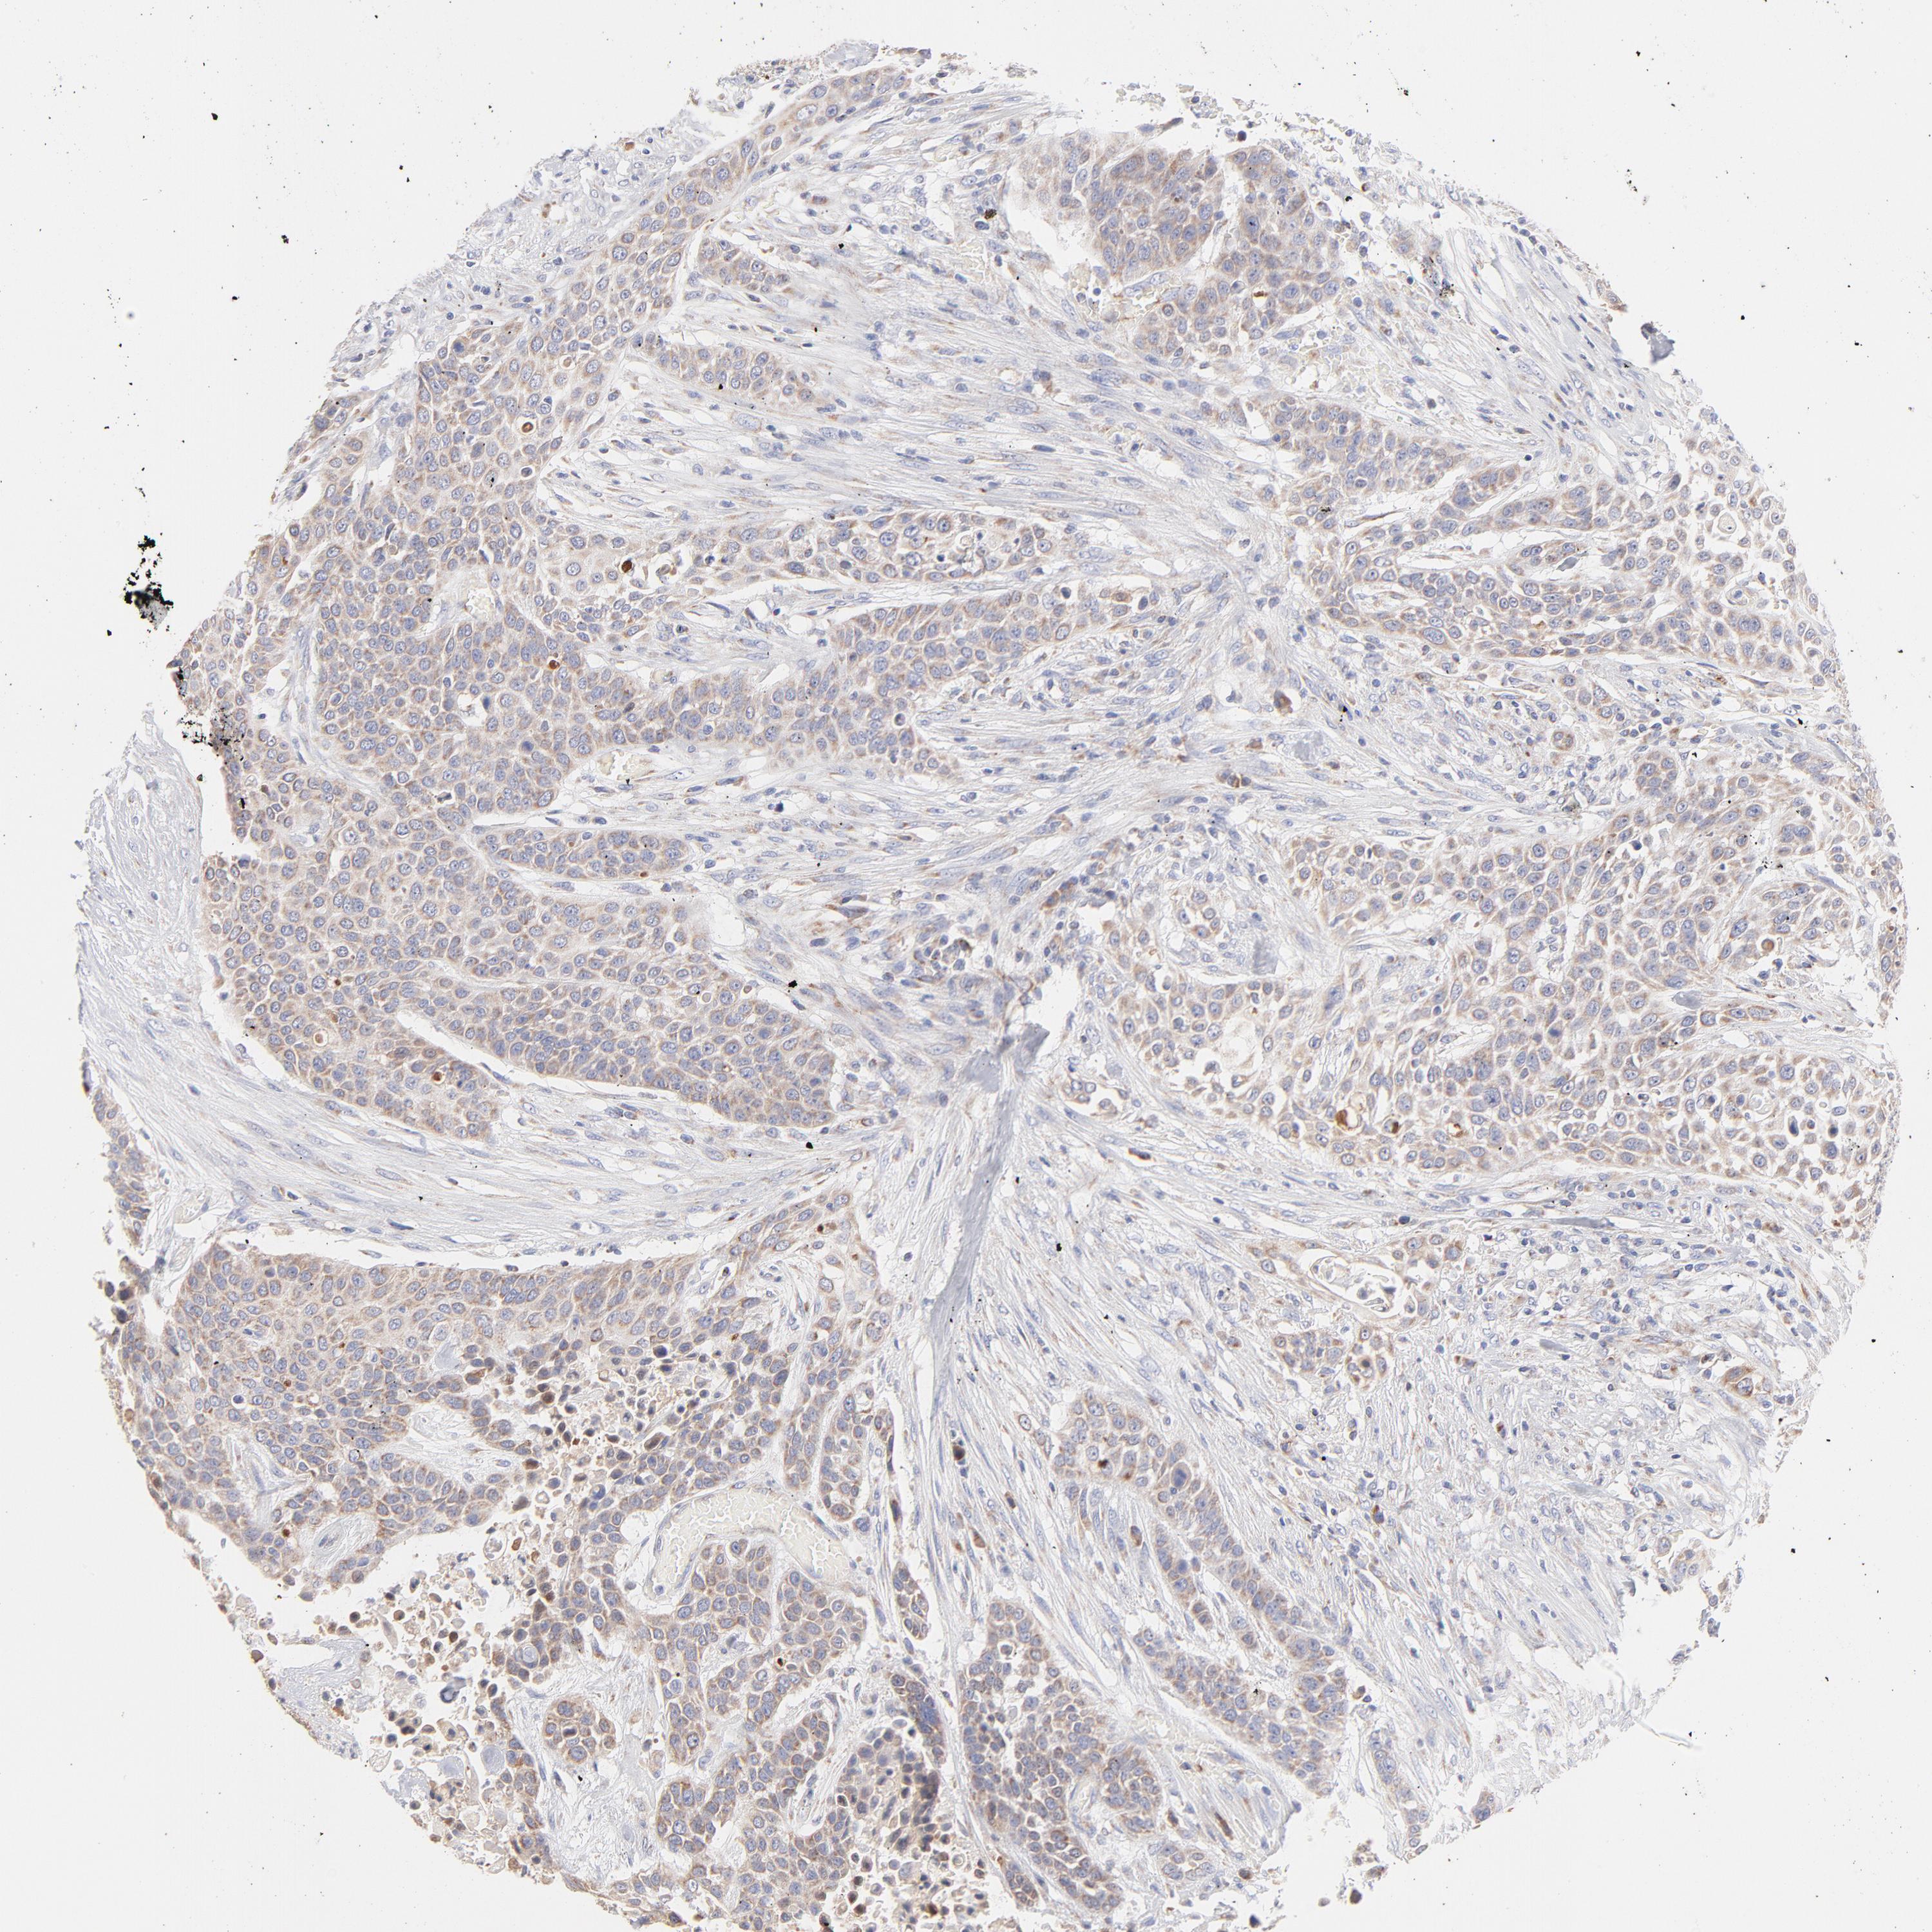

UROTHELIAL CANCER - Protein expressioni

A mouse-over function shows sample information and annotation data. Click on an image to view it in a full screen mode. Samples can be filtered based on level of antibody staining by selecting one or several of the following categories: high, medium, low and not detected. The assay and annotation is described here.

Note that samples used for immunohistochemistry by the Human Protein Atlas do not correspond to samples in the TCGA dataset.

Antibody stainingi

Antibody staining in the annotated cell types in the current human tissue is reported as not detected, low, medium, or high, based on conventional immunohistochemistry profiling in selected tissues. This score is based on the combination of the staining intensity and fraction of stained cells.

Each image is clickable and will lead to virtual microscopy that enables deeper exploration of all samples and also displays staining intensity scores, fraction scores and subcellular localization as well as patient and tissue information for each sample.

Antibody HPA003628

Staining

High

Medium

Low

Not detected

Intensity

Strong

Moderate

Weak

Negative

Quantity

>75%

75%-25%

<25%

None

Location

Nuclear

Cytoplasmic/membranous

Cytoplasmic/membranous,nuclear

Urothelial carcinoma, High grade

Urothelial carcinoma, Low grade